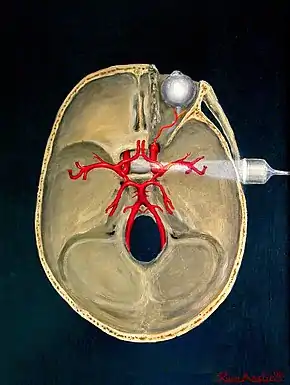

Transcranial

Transcranial Doppler (TCD) and transcranial colour Doppler (TCCD) measure the velocity of blood flow through the brain's blood vessels transcranially (through the cranium). These modes of medical imaging conduct a spectral analysis of the acoustic signals they receive and can therefore be classified as methods of active acoustocerebrography. They are used as tests to help diagnose emboli, stenosis, vasospasm from a subarachnoid hemorrhage (bleeding from a ruptured aneurysm), and other problems. These relatively quick and inexpensive tests are growing in popularity. The tests are effective for detecting sickle cell disease, ischemic cerebrovascular disease, subarachnoid hemorrhage, arteriovenous malformations, and cerebral circulatory arrest. The tests are possibly useful for perioperative monitoring and meningeal infection.[7] The equipment used for these tests is becoming increasingly portable, making it possible for a clinician to travel to a hospital, to a doctor's office, or to a nursing home for both inpatient and outpatient studies. The tests are often used in conjunction with other tests such as MRI, MRA, carotid duplex ultrasound and CT scans. The tests are also used for research in cognitive neuroscience.